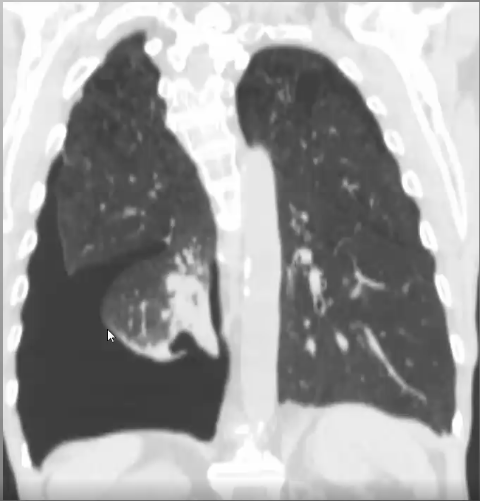

What’s your diagnosis?

Right lower lobe pneumonia because you have a right heart border (no silouhette sign) and a spine sign